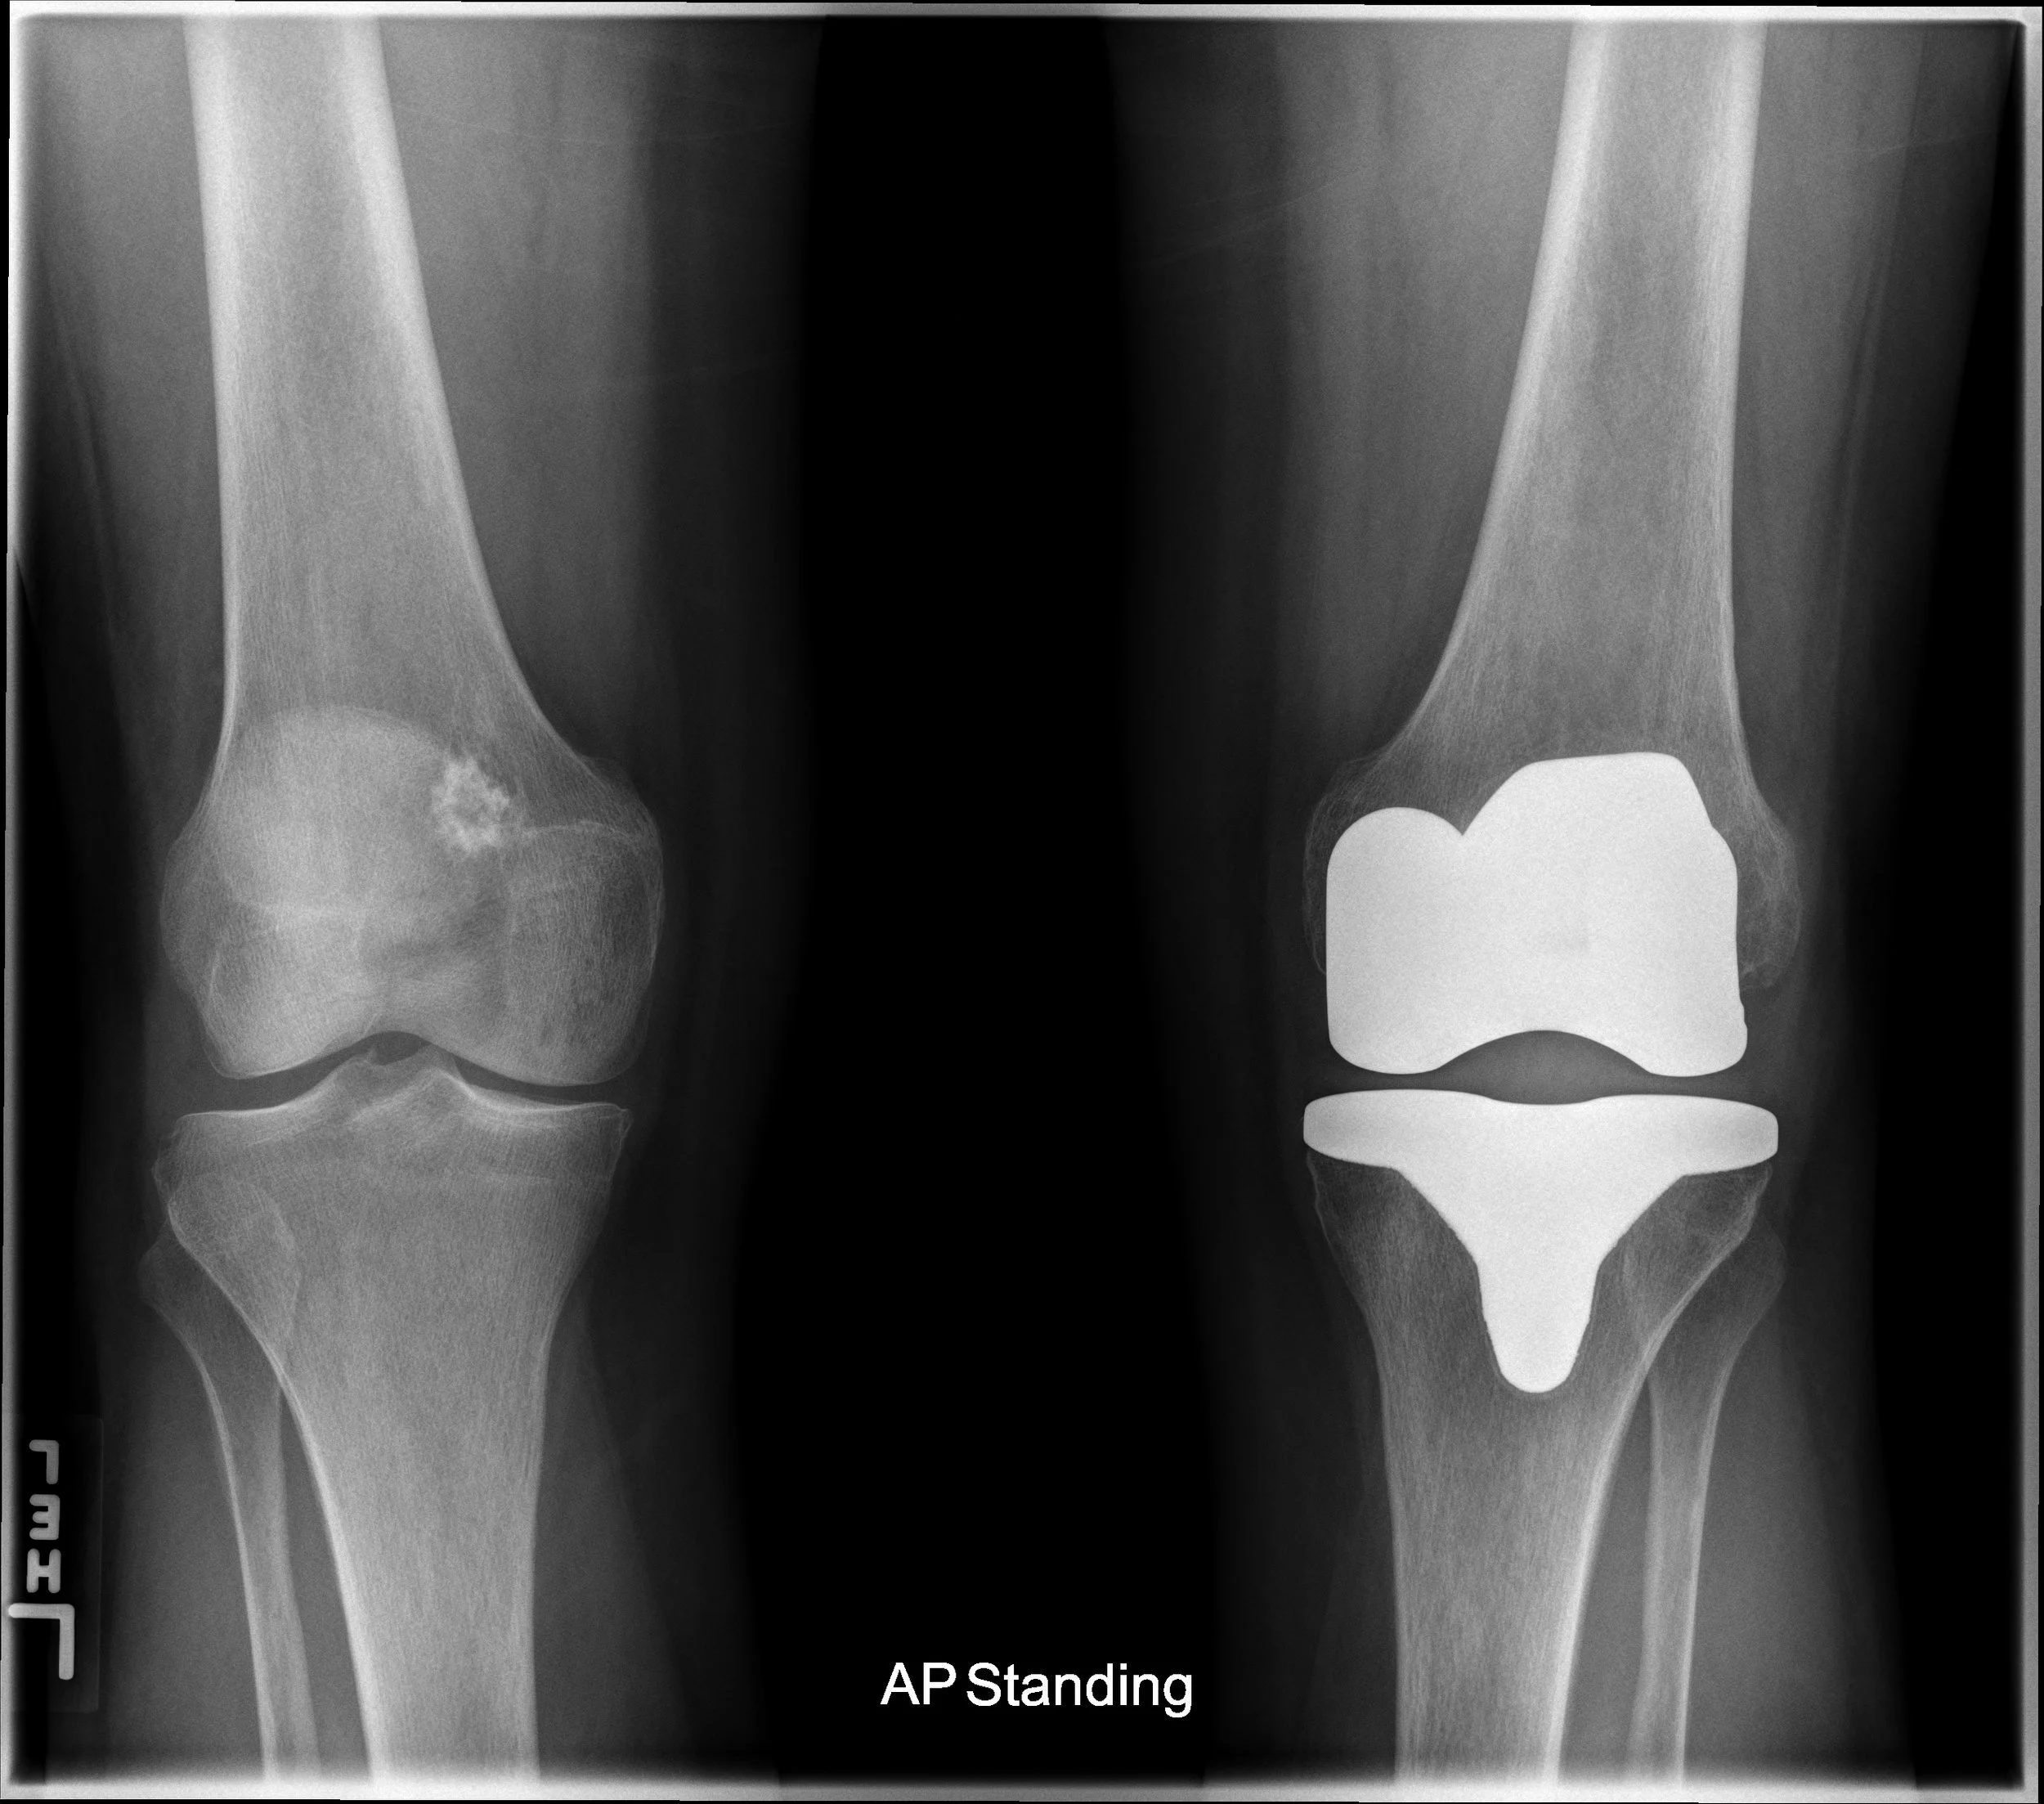

Case 167 Benign vs. malignant bone mass — DartRad Malignant Vs Basket Case But it won’t be sitting next to wan’s high points. He draws attention to a locked wicker basket that he goes around with. She's a real basket case. Gabriel may vs belial bradley (malignant vs basket case) thumbnail drawing matchup art share add a comment. “malignant” is going to have a place in the pantheon of horror film. Basket case. Malignant Vs Basket Case.